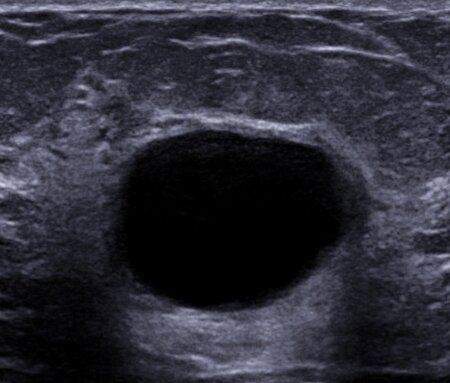

به گزارش بهداشت نیوز، شایعترین علت تودههای خوشخیم پستانی «بیماری فیبروکیستیک» است که بیش از همه در سنین ۳۰ تا ۵۰ بروز میکند. در این بیماری مجموعهای از کیستها یا کیسههای کوچک در پستان ایجاد میشود که برخی از آن توپر و برخی دیگر پر از مایع هستند. اندازه این کیستها اغلب در هفته پیش از قاعدگی اندازهشان افزایش پیدا میکند و حساستر هم میشوند.

این کیستها به صورت تودههایی در ماموگرافی و سونوگرافی هم ظاهر میشوند و پزشکتان ممکن است برای اطمینان یافتن از غیرسرطانی بودنشان از آنها نمونهبرداری کند.

گاهی به جای اینکه بافت جوشگاهی در محل آسیب دیدن بافت چربی ایجاد شود، سلولهای چربی که مردهاند چربی درون خود را ازاد میکنند و یک کیست روغنی ایجاد میشود که میتوان با سوزن و سرنگ آن را تخلیه کرد.